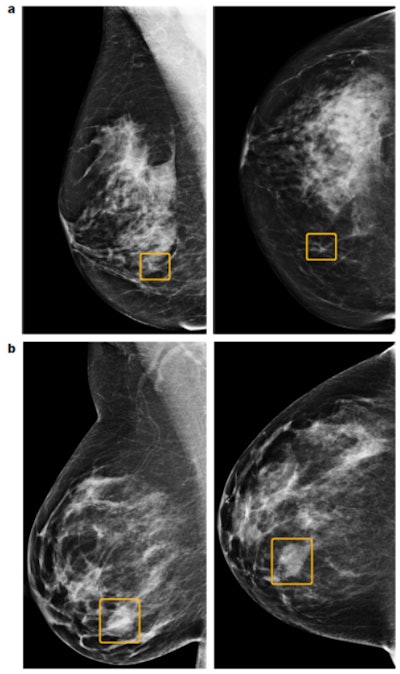

Discrepancies between the AI system and human readers. The top images (a) show a sample cancer case that was missed by all six readers in the U.S. reader study but correctly identified by the AI system. The malignancy, outlined in yellow, is a small, irregular mass with associated microcalcifications in the lower inner right breast. The bottom two images (b) show a sample cancer case that was caught by all six readers in the U.S. reader study but missed by the AI system. The malignancy is a dense mass in the lower inner right breast. Left = mediolateral oblique view; right = craniocaudal view. Images courtesy of Scott Mayer McKinney and colleagues and Nature.Double reading and workload